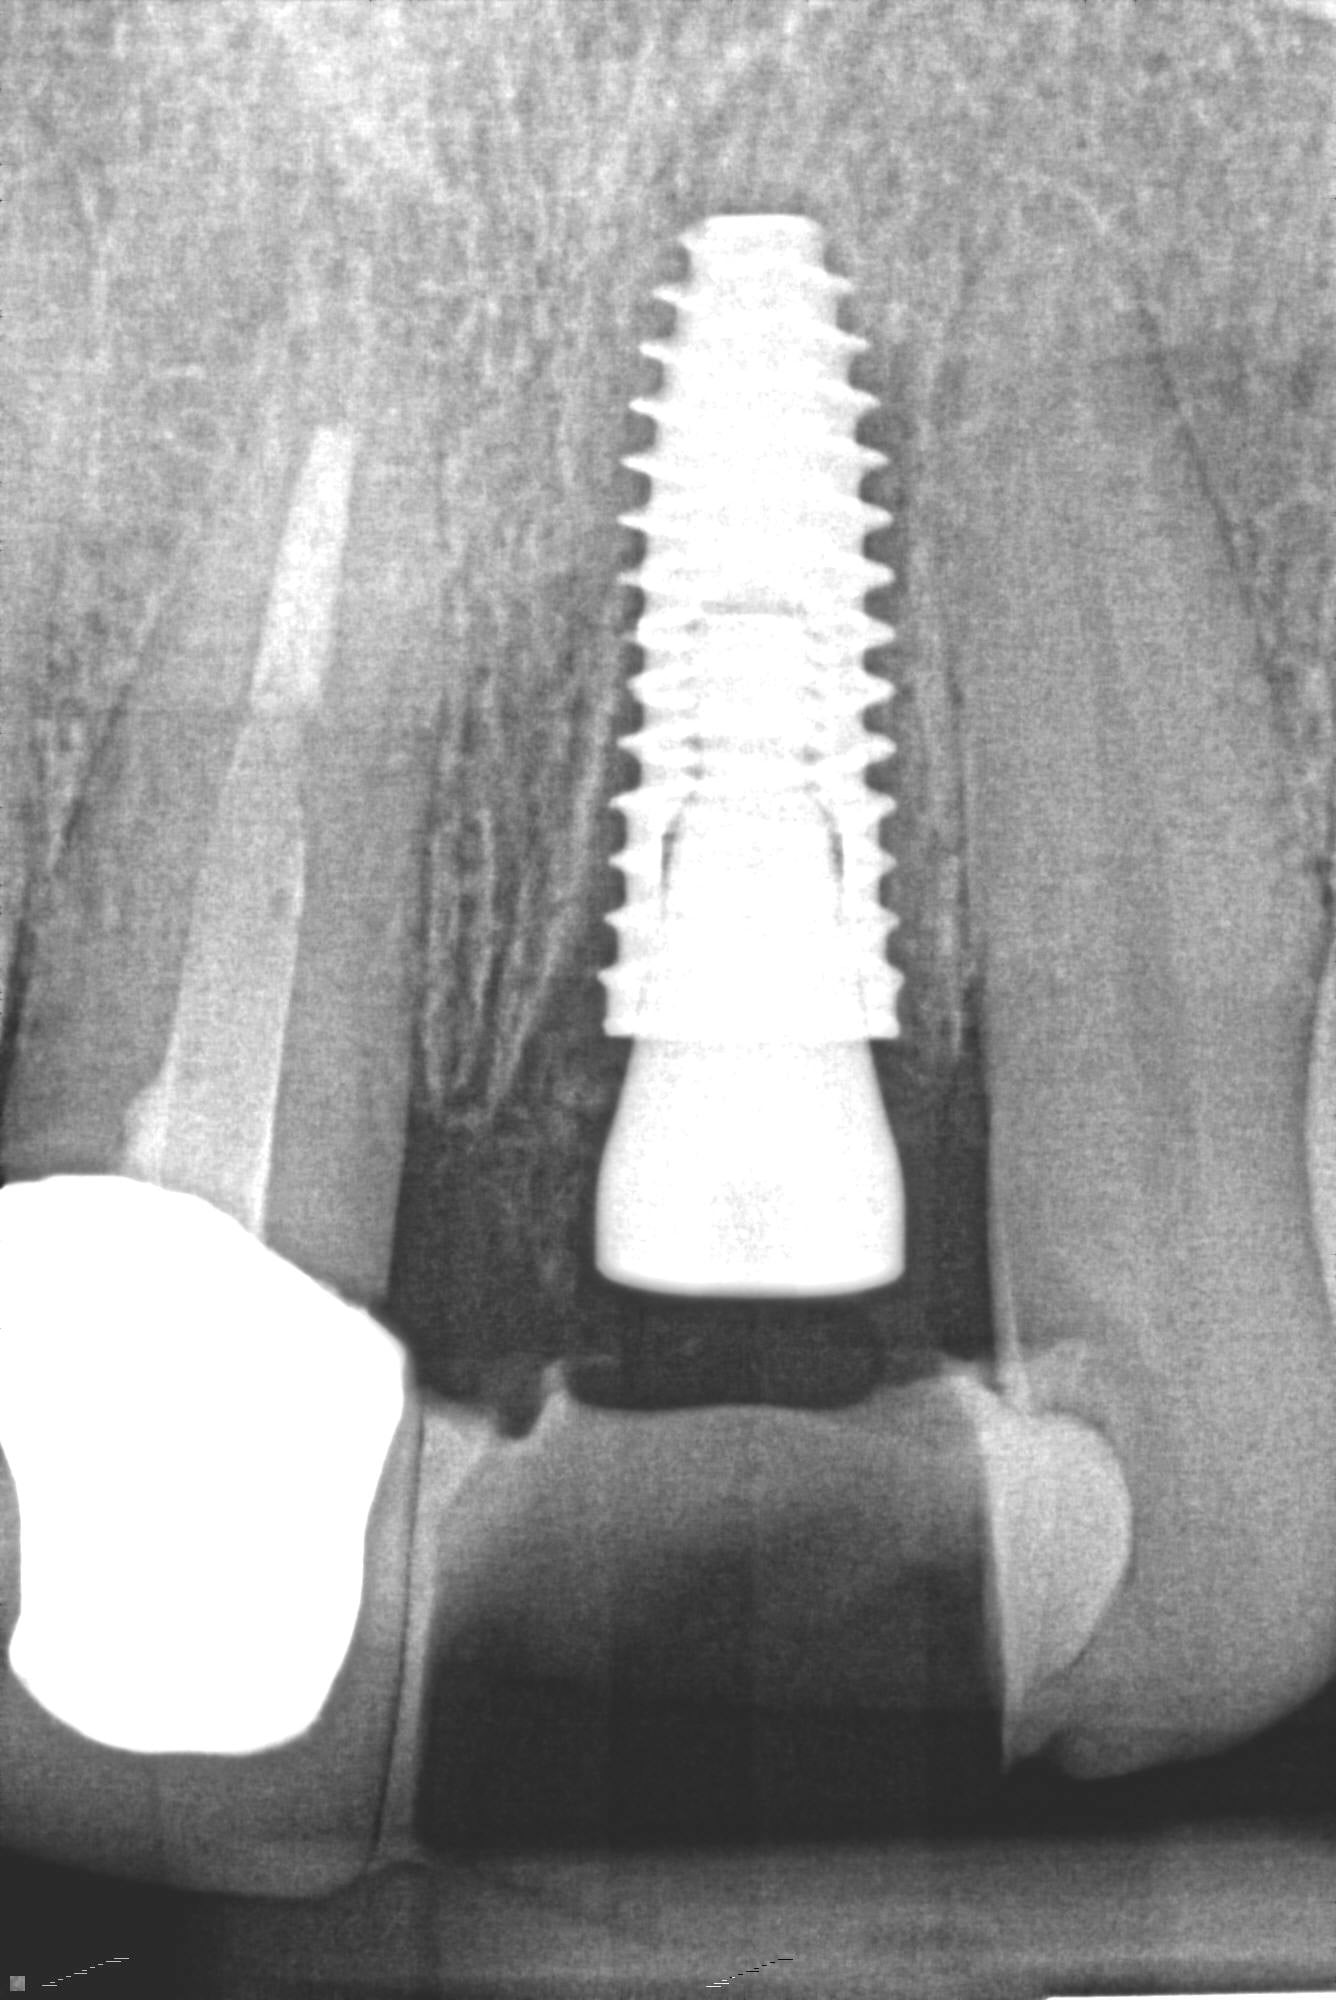

3. What option can describe the post placement in the X ray bellow for the tooth # 3.6?